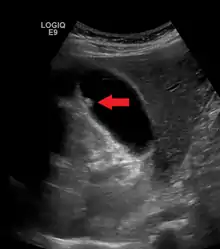

A polyp in the gall bladder as seen on ultrasound

Gallbladder polyps are growths or lesions resembling growths (polypoid lesions) in the wall of the gallbladder. True polyps are abnormal accumulations of mucous membrane tissue that would normally be shed by the body.

Diagnosis is typically by ultrasound or CT imaging.